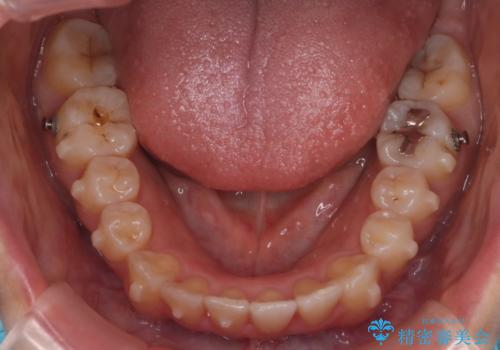

【インビザライン】マウスピースで開咬改善

歯の移動量が多いケースでしたが、患者様にマウスピースの使用とゴム掛けを頑張っていただいたので

リファイメント1回のみで治療を終わることができました。